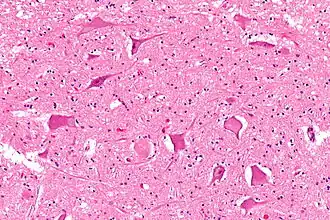

Central chromatolysis is the most common form of chromatolysis and is characterized by the loss or dispersion of the Nissl bodies starting near the nucleus at the center of the neuron, and then extending peripherally towards the plasma membrane. Also characteristic of central chromatolysis is the displacement of the nucleus towards the periphery of the perikaryon.[3][4][5] Other cellular changes are observed during the process of the central chromatolysis. The process of Nissl dissolution is less apparent toward periphery of the cell body of the neuron, where normal-looking Nissl bodies may be present.[1] Hyperplasia of neurofilaments is frequently observed, however the extent varies. The number of autophagic vacuoles and lysosomal structures often increase during central chromatolysis. Changes can also occur in other organelles such as the Golgi apparatus and neurotubules. However, the exact significance of these changes is currently unknown. In neurons receiving axonal transection, central chromatolysis is observed in the area between the nucleus and the axon hillock following.[6]

Peripheral chromatolysis is much less common, but has been reported to occur after axotomy and ischemia in certain species. Peripheral chromatolysis is essentially the reverse of central chromatolysis, in which the disintegration of Nissl bodies is initiated at the periphery of the neuron and extends inwards towards the nucleus of the cell. Peripheral chromatolysis has been observed to occur in lithium-induced chromatolysis and it could be useful in investigating and countering the hypothesis that waves of enzymatic activity always progress from the perinuclear area, or the area situated around the nucleus, to the peripheral of the cell.[7]